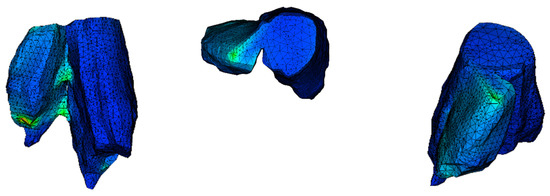

In comparison with industrial models, which are studied through computational methods, in biomechanics the object is not designed with a CAD software and its geometry varies randomly from person to person. In order to identify that the one and only fracture is the posterior malleolus fracture, all the ankle joint parts were thoroughly observed. The software RETOMO, as a tool, gave us the opportunity to run a 3D view around the CT scan and focus further on the fracture location. In practice, the tree dimensional image is recognized through the software and converted in a surface within the boundaries that the image defines. Afterwards, the surface is meshed and replaced with face elements. The first indication that the fracture is posterior malleolus, is given as when only the tibia has a broken part and the fibula appears complete (Figure 1). A second verification is that no fracture appears on medial malleolus.

Figure 1. (a) Section cut of the posterior malleolus fracture; (b) plan view (fracture shown on the left).